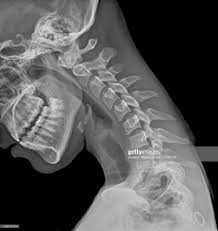

Normal Cervical Spine X Ray Stock Image C039 3921 Science Photo Library from media.sciencephoto.com It's commonly done after someone has been in an automobile or other accident. Enter search terms and tap the search button. Here's what to expect with this painless procedure and why your dentist may recommend it. They show pictures of your internal tissues, bones, and organs. Please understand that our phone lines must be clear for urg. This procedure may be used to diagnose back or neck pain, fractures or broken bones, arthritis, degeneration of the disks, tumors, or other problems.

This procedure may be used to diagnose back or neck pain, fractures or broken bones, arthritis, degeneration of the disks, tumors, or other problems. Enter search terms and tap the search button. They show pictures of your internal tissues, bones, and organs. Please understand that our phone lines must be clear for urg. Here's what to expect with this painless procedure and why your dentist may recommend it.